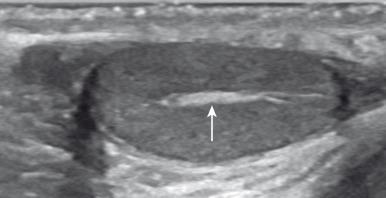

Figure 125.3, Mediastinum testis.

The testes should be ovoid, nearly symmetric, and homogeneously echogenic. There is some discrepancy with regard to normal testicular volumes ( Box 125.1 ). A highly echogenic linear focus (seen posteriorly and superiorly) represents the mediastinum testis ( Fig. 125.3 ), which is the inward extension of the tightly adherent covering of the testis, the tunica albuginea. Fibrous septa extending from the mediastinum testes divide the testes into more than 250 lobules, each drained by one or more seminiferous tubules that merge into the rete testes. The rete testes, draining veins, lymphatics, nerves, and testicular artery course within the mediastinum testis.